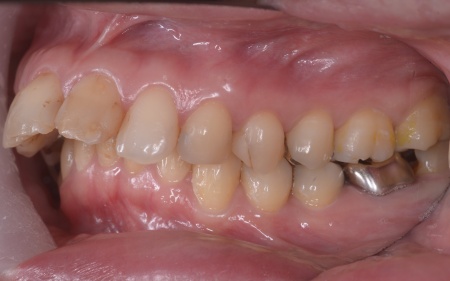

| 相談内容 | 「昔から出っ歯が気になっていて、治したいと思っていた。また、噛み合わせが悪く奥歯に負担がかかっていて、噛むと痛いことがある」とご相談いただきました。 |

| カウンセリング | 拝見したところ、上前歯が大きく前に出ている上顎前突であり、上下の前歯が噛み合わずに口を閉じても前歯同士が接触しない「開咬(かいこう)」の状態でした。 レントゲン撮影をして詳しく調べた結果、歯の位置だけでなく、骨格的な問題があることが分かりました。 また、前歯で食べ物をうまく噛み切ることができないため、奥歯にも強い負担がかかっているだけでなく、このまま放置すると、奥歯がすり減ったり痛みが生じたりするリスクもあります。 以上のことから、噛み合わせを改善する治療が必要だと診断しました。 |